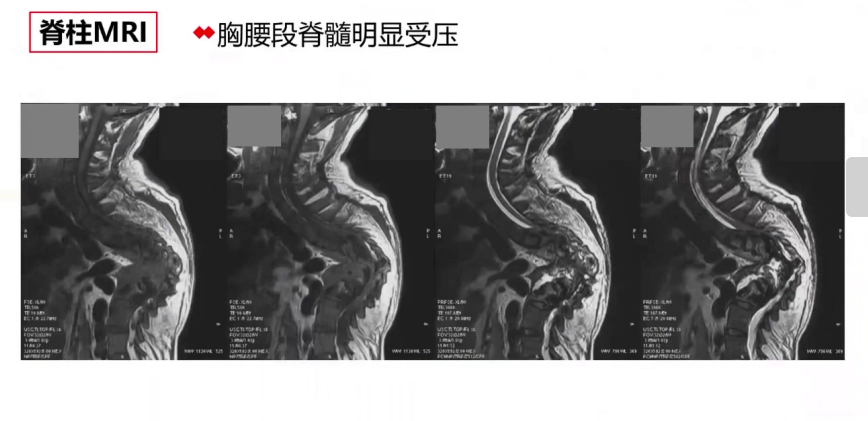

实验室检查血常规、血生化、凝血功能和血气基本正常,心脏超声提示心脏无器质性功能异常,胸部CT显示呈桶状胸,前后径大于10左右,其余无明显异常,3D打印提示自胸3至腰3椎体后柱及融合椎体畸形,胸主动脉磁共振提示胸腰段脊髓明显受压。